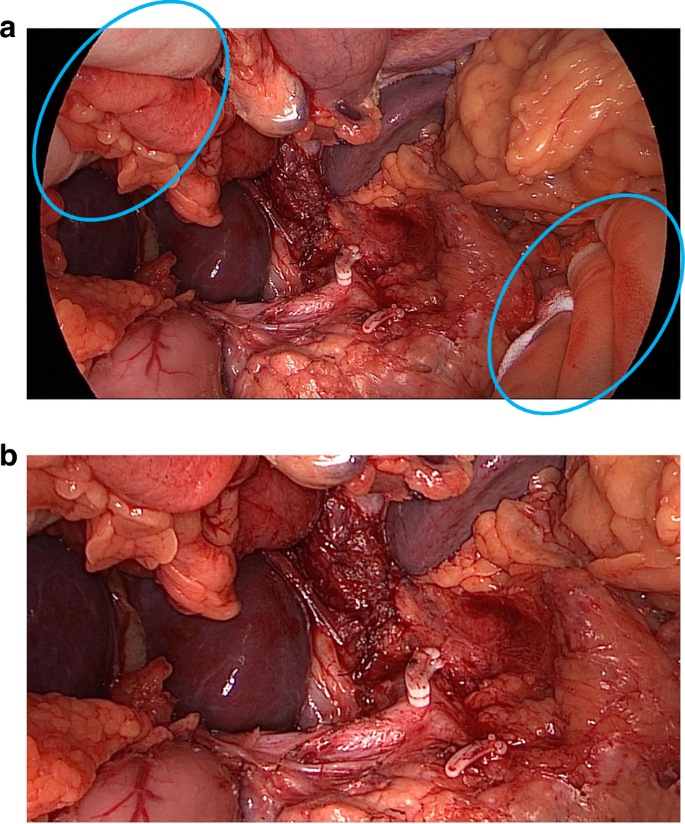

Another problem was that some photographs revealed the treatment allocation (i.e. whether it was OO or LAO). Common reasons for this were visible procedure-specific surgical instruments or gloved hands (indicating OO). Post-production editing was undertaken to crop identifiers out of view to ensure that assessors could remain blinded (Fig. 1) to the randomised allocation. Occasionally, this was not possible due to the proximity of the identifiers to important anatomical structures. In this scenario, we placed ‘black boxes’ over the identifiers to mask them (Fig. 2). The shape and/or size of the black boxes was purposefully changed throughout to avoid identification of procedure type related to the position of the instruments or hands.

Image a shows identifiable objects requiring anonymisation, and image b shows the cropped image to achieve this.